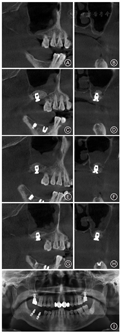

炎症组典型病例 患者,男,56岁,2015年12月就诊,主诉:牙齿缺失求治。现病史,牙齿因松动拔除数年,现要求种植修复。检查:17、27、46、47缺失,缺牙区宽度可,龈无明显红肿,CBCT示17的RBH约1.5 mm,右上颌窦底黏膜厚约3 mm。诊断:牙列缺损。治疗:17、27行上颌窦底外提升术同期种植术,46、47行种植修复,种植一期手术6个月后行种植修复。于2015年12月行17经外侧壁开窗的上颌窦底提升术同期植入种植体,术中将上颌窦底黏膜提升,未出现上颌窦底黏膜穿孔,术后CBCT示提升效果可。术后7 d复诊出现上颌窦急性炎症症状,给予抗炎对症治疗,3 d后症状消失,术后6个月行二期修复。术后6个月随访,CBCT示种植体无明显骨吸收,上颌窦提升成骨效果可,上颌窦黏膜较术前有所增厚。该患者手术前后及随访影像学资料见图2。